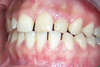

Notre patiente ne sourit pas à cause de sa dent naine à droite et de ses espaces interdentaires.

Avant l'opération